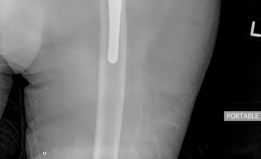

--- Fig. 19.10 The final implant used had been templated as a backup preoperatively. A 3D printed model was generated from the CT and was then reamed for placement of the jumbo cup with augment. The augment fills the superior defect while the jumbo cup fills in the medial and inferior defects femoral head component was disimpacted and removed. The femoral stem was checked and noted to be in good position and stable and therefore, it was maintained. Attention was then turned to the acetabular component, which was grossly loose. There was a massive amount of bone loss encountered, and a Paprosky type IIIB defect was confirmed. An attempt was made to insert the custom cage; however, there was not a proper fit, and this was abandoned. The remaining acetabulum was reamed to accept a size 78 mm jumbo porous metal shell. The superior acetabular defect was augmented with an augment measuring 50 × 10 mm with two screws providing fixation. The acetabulum was then bone grafted with a combination of cancellous allograft and demineralized bone matrix. The acetabular cup was

impacted into place, and three screws were utilized for supplemental fixation. The interface between the acetabular component and the augment was then cemented. A 36, 0-degree liner was utilized. Trial and final reduction of the hip revealed excellent leg length, stability, and range of motion. The incision was copiously irrigated at multiple points during the case and the incision was closed in layers (Fig. 19.11).

Postoperative Radiographs

(Fig. 19.11)